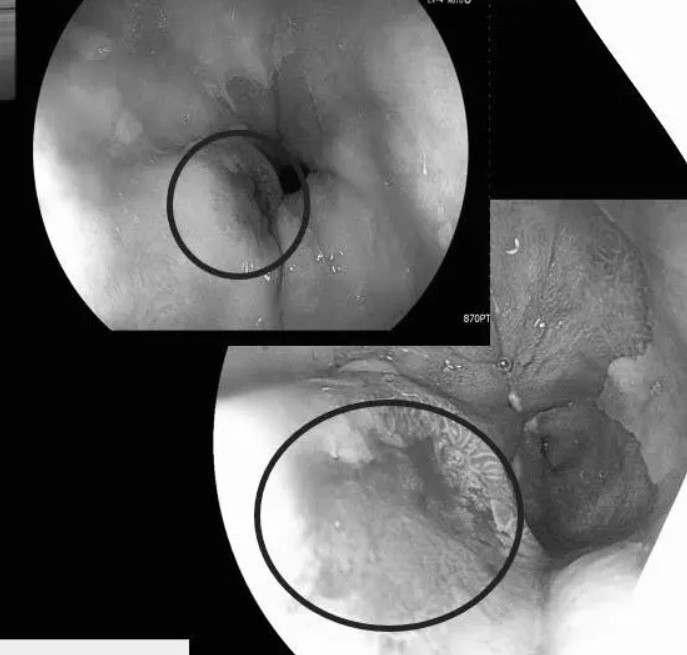

Qua nội soi thực quản - dạ dày, các bác sĩ phát hiện đoạn 1/3 dưới thực quản bệnh nhân có vết loét khoảng 8mm. Kết quả sinh thiết cho thấy ông bị ung thư thực quản.

Sau hội chẩn giữa các bác sĩ Nhật Bản và Bệnh viện Chợ Rẫy, bệnh nhân được phẫu thuật thành công, đồng thời còn cắt bỏ thêm polyp đại tràng nghịch sản nặng nhờ may mắn phát hiện, tránh thêm được một nguy cơ ung thư.